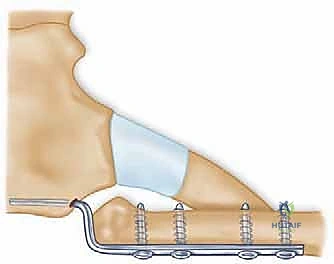

لا يمكن ببساطة خياطة الأربطة الممزقة لضمان الاستقرار. لذلك، يستخدم الدكتور هطيف تقنية متقدمة لإعادة البناء باستخدام "رقعة وترية" (Tendon Graft).

* أخذ الرقعة: غالباً ما تؤخذ من وتر العضلة الرشيقة (Gracilis) أو العضلة نصف الوترية (Semitendinosus) من ركبة المريض نفسه (Autograft)، أو استخدام رقعة صناعية طبية عالية الجودة.

* حفر الأنفاق العظمية: يتم حفر ثقوب دقيقة جداً في عظم الترقوة وعظم القص باستخدام أدوات جراحية متطورة.

5. تمرير الرقعة وتثبيتها (تقنية الرقم 8)

يتم تمرير الرقعة الوترية عبر الثقوب العظمية بنمط يشبه الرقم 8 (Figure-of-eight). هذه التقنية الميكانيكية الحيوية توفر قوة استقرار هائلة تحاكي قوة الأربطة الطبيعية (الرباط الكبسولي والرباط الضلعي الترقوي).

تحذير طبي هام: في الماضي، كان بعض الجراحين يستخدمون أسياخ معدنية (K-wires) لتثبيت المفصل. الأستاذ الدكتور محمد هطيف يمنع تماماً استخدام هذه الأسياخ في هذا المفصل، حيث أثبتت الدراسات الطبية أن هذه الأسياخ قد تهاجر وتخترق القلب أو الرئتين مسببة الوفاة. بدلاً من ذلك، يعتمد الدكتور هطيف على خيوط جراحية فائقة القوة (Suture anchors) والرقع الوترية الطبيعية التي تندمج مع الجسم.